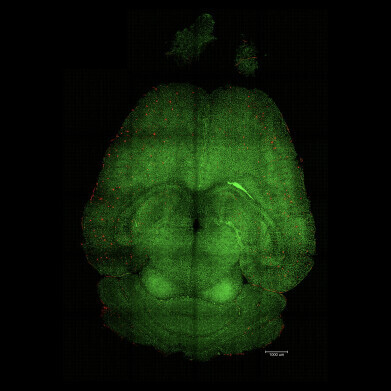

Light sheet fluorescence microscope images of mouse brain 12h after NOT being treated with nanoparticles. The brains were analysed to see the amount of Aβ plaques accumulation. Red: Aβ plaques. Green: vessels from the blood brain barrier. Credit: Institute for Bioengineering of Catalonia -

Light sheet fluorescence microscope image of mouse brain 12h after being treated with nanoparticles. The brains were analysed to see the amount of Aβ plaques accumulation. Red: Aβ plaques. Green: vessels from the blood brain barrier. Credit: Institute for Bioengineering of Catalonia